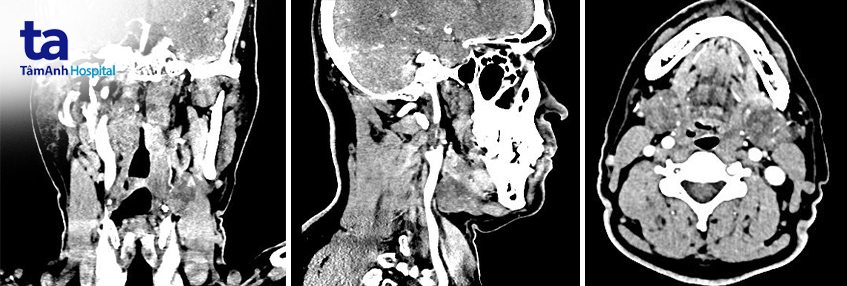

CT-scan hoặc MRI giúp đánh giá cấu trúc giải phẫu của khối u.